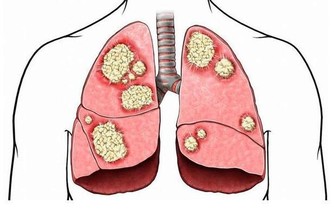

腦動脈硬化病病人

多吃血管清道夫預防腦梗塞

血液垃圾太多、血管老化都會使血管變窄堵塞,飲食上可多吃一些具有清理血液垃圾,養護血管功效的食物或保健品。綠茶裡的茶多酚具有抗氧化作用,而且綠茶中的綠茶素具有抑制血栓形成的作用,都可以保護心腦血管。